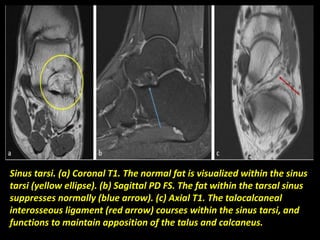

Sinus tarsi. (a) Coronal T1. The normal fat is visualized within the sinus

tarsi (yellow ellipse). (b) Sagittal PD FS. The fat within the tarsal sinus

suppresses normally (blue arrow). (c) Axial T1. The talocalcaneal

interosseous ligament (red arrow) courses within the sinus tarsi, and

functions to maintain apposition of the talus and calcaneus.

Sinus tarsi. (a)Coronal T1. The normal fat is visualized within the sinus tarsi (yellow ellipse). (b) Sagittal PD FS. The fat within the tarsal sinus suppresses normally (blue arrow). (c) Axial T1. The talocalcaneal interosseous ligament (red arrow) courses within the sinus tarsi, and functions to maintain apposition of the talus and calcaneus.